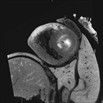

Caption Play Movie2D Serial EFIC image stack in the transverse view of 464-003-NA reveals hypoplastic aortic arch and aortic valve, hypoplastic left ventricle with small mitral valve.

Copyright This image is from the Laboratory of Dr. Cecilia Lo, a member of the Cardiovascular Development Consortium (CvDC), Bench to Bassinet (B2B) program of the National Heart Lung and Blood Institute (NHLBI), and is displayed with the permission of the authors. J:175213